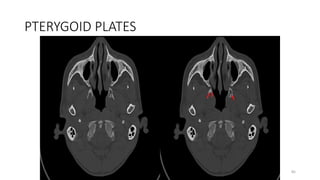

PTERYGOID PLATES